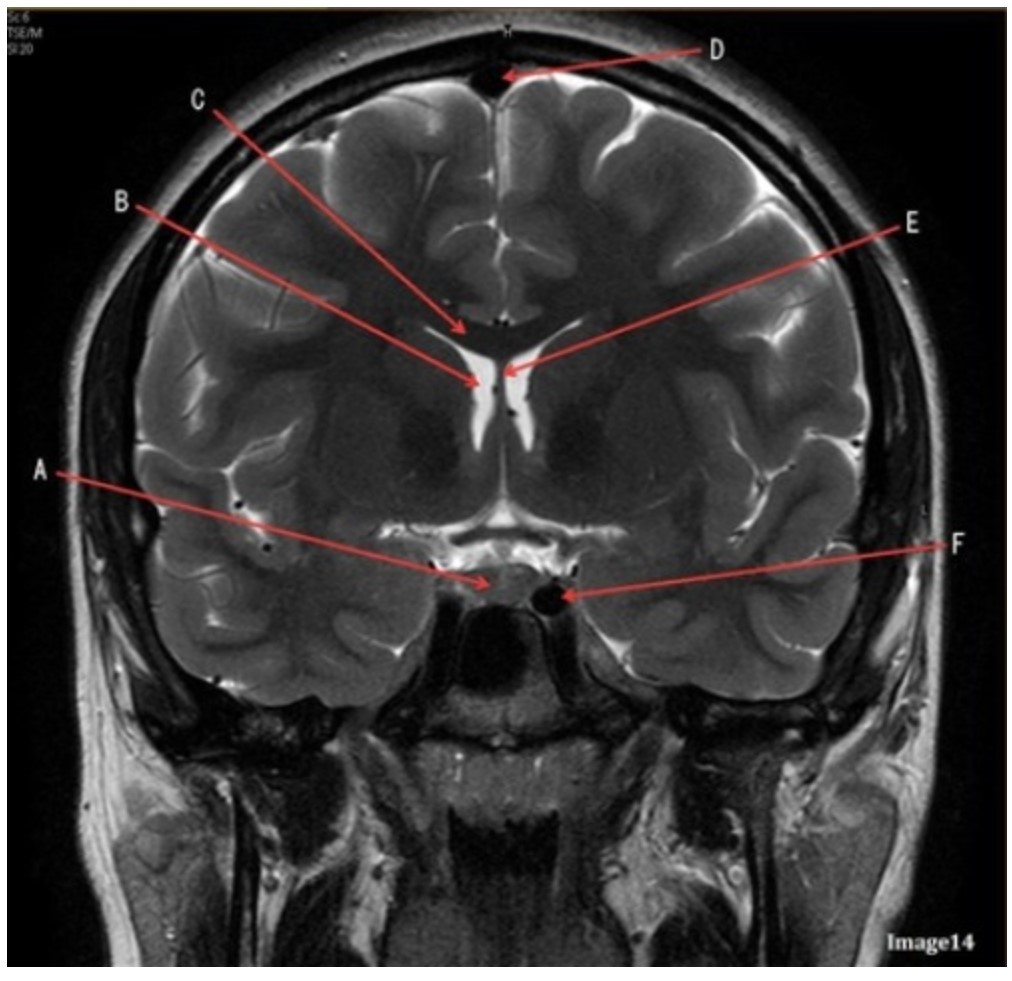

Letter F in Image 14 is pointing to:

A. Third ventricle

B. Pituitary gland

C. Hypothalamus

D. Internal carotid artery

Letter C in Image 14 is pointing to:

A. Corpus callosum

B. Third ventricle

C. Lateral ventricle

D. Pituitary gland

E. Fornix

Letter D in Image 14 is pointing to:

A. Tentorium

B. Sphenoid sinus

C. Frontal sinus

D. Sagittal sinus

E. Fornix

Letter B in Image 14 is pointing to:

A. Corpus callosum

B. Third ventricle

C. Lateral ventricle

D. Pituitary gland

E. Fornix

Letter E in Image 14 is pointing to:

A. Corpus callosum

B. Third ventricle

C. Lateral ventricle

D. Internal carotid artery

E. Fornix

Letter A in Image 14 is pointing to:

A. Corpus callosum

B. Third ventricle

C. Lateral ventricle

D. Pituitary gland

E. Fornix

Letter A in Image 14 is pointing to:

A. Corpus callosum

B. Third ventricle

C. Lateral ventricle

D. Pituitary gland

E. Fornix